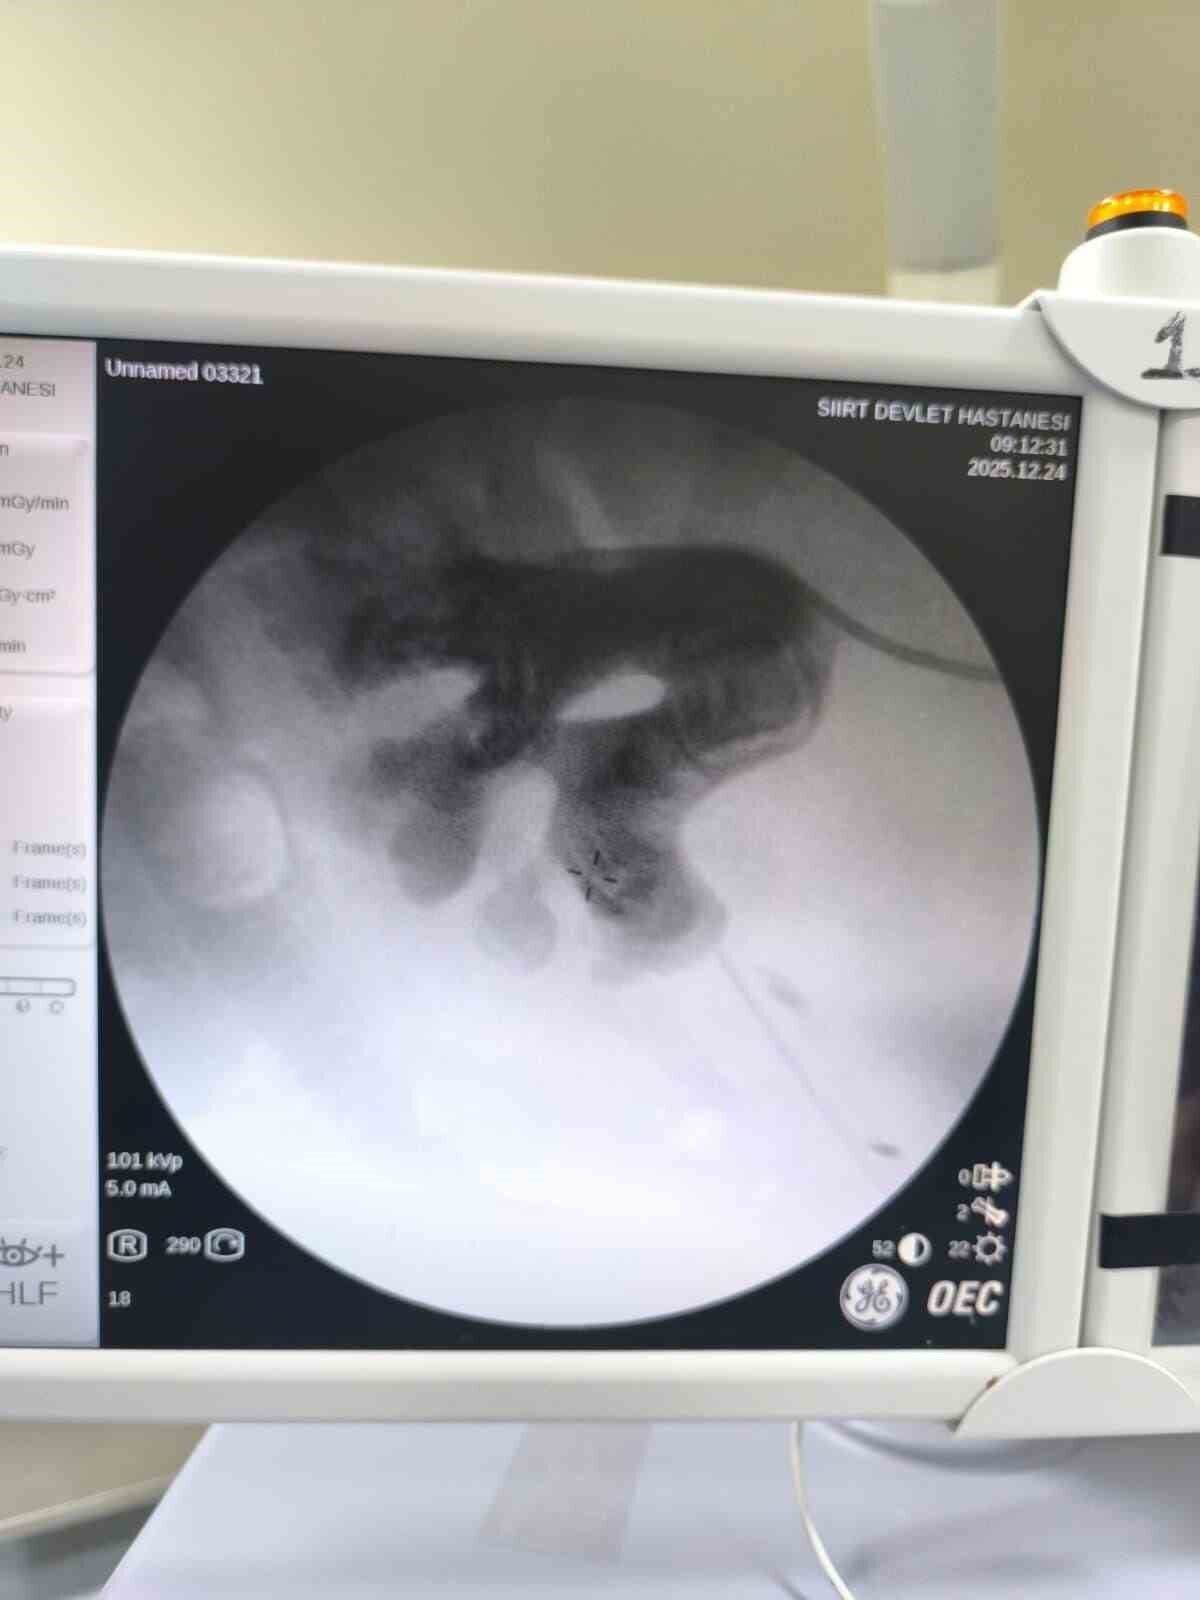

Siirt’te 34 yaşındaki Fatih Aslan, ateş, üşüme ve idrar yaparken yanma şikayetleriyle hastaneye başvurdu. Yapılan muayene ve testlerin ardından piyelonefrit (böbrek iltihabı) tanısı konuldu ve enfeksiyon tedavisi başarıyla tamamlandı. Üroloji uzmanı doktor Miraç Ataman, gerçekleştirilen operasyonun hem tıbbi açıdan hem de toplumsal sağlık açısından önemli bir başarı olduğunu ifade etti. Ataman, “34 yaşındaki erkek hastamız, ateş, üşüme ve idrar yaparken yanma şikayetleri ile acil servise başvurdu. Yapılan değerlendirme sonunda piyelonefrit (böbrek iltihabı) tanısı konuldu ve yatağa alınarak enfeksiyon tedavisi başarıyla tamamlandı. Tanı sürecinde yapılan Bilgisayarlı Tomografi (BT) görüntülemesinde böbreğin tamamını kaplayan, sert yapıda (950-1450 HU), literatürde staghorn olarak adlandırılan ve halk arasında ‘geyik boynuzu taşı’ olarak bilinen büyük taş tespit edildi. Staghorn taşlar, böbreğin tüm boşluklarını doldurduğundan, tekrarlayan enfeksiyonlara ve uzun vadede böbrek fonksiyon kaybına yol açabilmektedir. Bu sebeple tedavisi hayati önem taşımaktadır. Biz de bu vakamızda, Perkütan Nefrolitotomi (PCNL) yöntemiyle böbreğe küçük bir cilt kesisi üzerinden girerek endoskopik cihazlarla taşları parçalayıp çıkardık. PCNL, özellikle çapı 2 cm’den büyük ve karmaşık taşlarda altın standart olarak kabul edilmektedir. Normalde staghorn taşların temizlenmesi uzun süren ve çoğu zaman birden fazla seans gerektiren zorlu bir süreçtir. Modern altyapısı sayesinde, ciltten tek bir giriş yolu açılarak yaklaşık 1,5 saatlik bir seansta böbreğin tüm taş yükü başarıyla temizlendi” dedi.